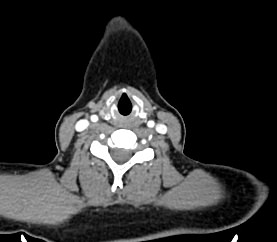

Мультиспиральная компьютерная томография – это высокоинформативный лучевой метод диагностики различной патологии мягких тканей шеи, включая воспалительные заболевания, травматические повреждения и опухолевые процессы. КТ позволяет оценить состояние щитовидной железы, паращитовидных желез, гортани, верхней части пищевода, магистральных сосудов шеи, шейных лимфоузлов и окружающих мягких тканей.

Метод КТ основан на применении рентгеновского излучения. Однако в отличие от обычного рентгена, при котором снимки производятся в одной плоскости, при КТ излучатель рентгеновских лучей постоянно двигается вокруг объекта исследования, проводя сканирование в различных плоскостях, а затем трансформируя полученные данные в цифровые трехмерные изображения. Это дает возможность визуализировать органы и ткани в мельчайших подробностях, а с помощью объемных 3D-реконструкций наглядно оценить пространственное расположение органов и патологических образований.

Рентгеновские лучи лучше всего поглощаются плотными структурами, такими как костная ткань. Поэтому кости хорошо видны на снимках КТ. Это делает компьютерную томографию незаменимой при необходимости обследования, в частности, костного скелета гортани. Однако для улучшения визуализации мягких тканей требуется введение специального контрастного препарата, поэтому КТ мягких тканей шеи проводится с контрастным усилением.

Для контрастирования используется йодсодержащее контрастное вещество, которое в составе рентгеноконтрастного препарата вводится в вену пациенту непосредственно во время исследования. Благодаря способности контраста поглощать рентгеновские лучи на снимках КТ хорошо контрастируются кровеносные сосуды и опухолевые образования, имеющие, как правило, развитую сосудистую сеть. Методика внутривенного болюсного контрастирования помогает обнаружить воспалительные изменения, отличить доброкачественные опухоли от злокачественных, выявить поражение лимфатических узлов и степень прорастания опухоли в магистральные сосуды и окружающие ткани.